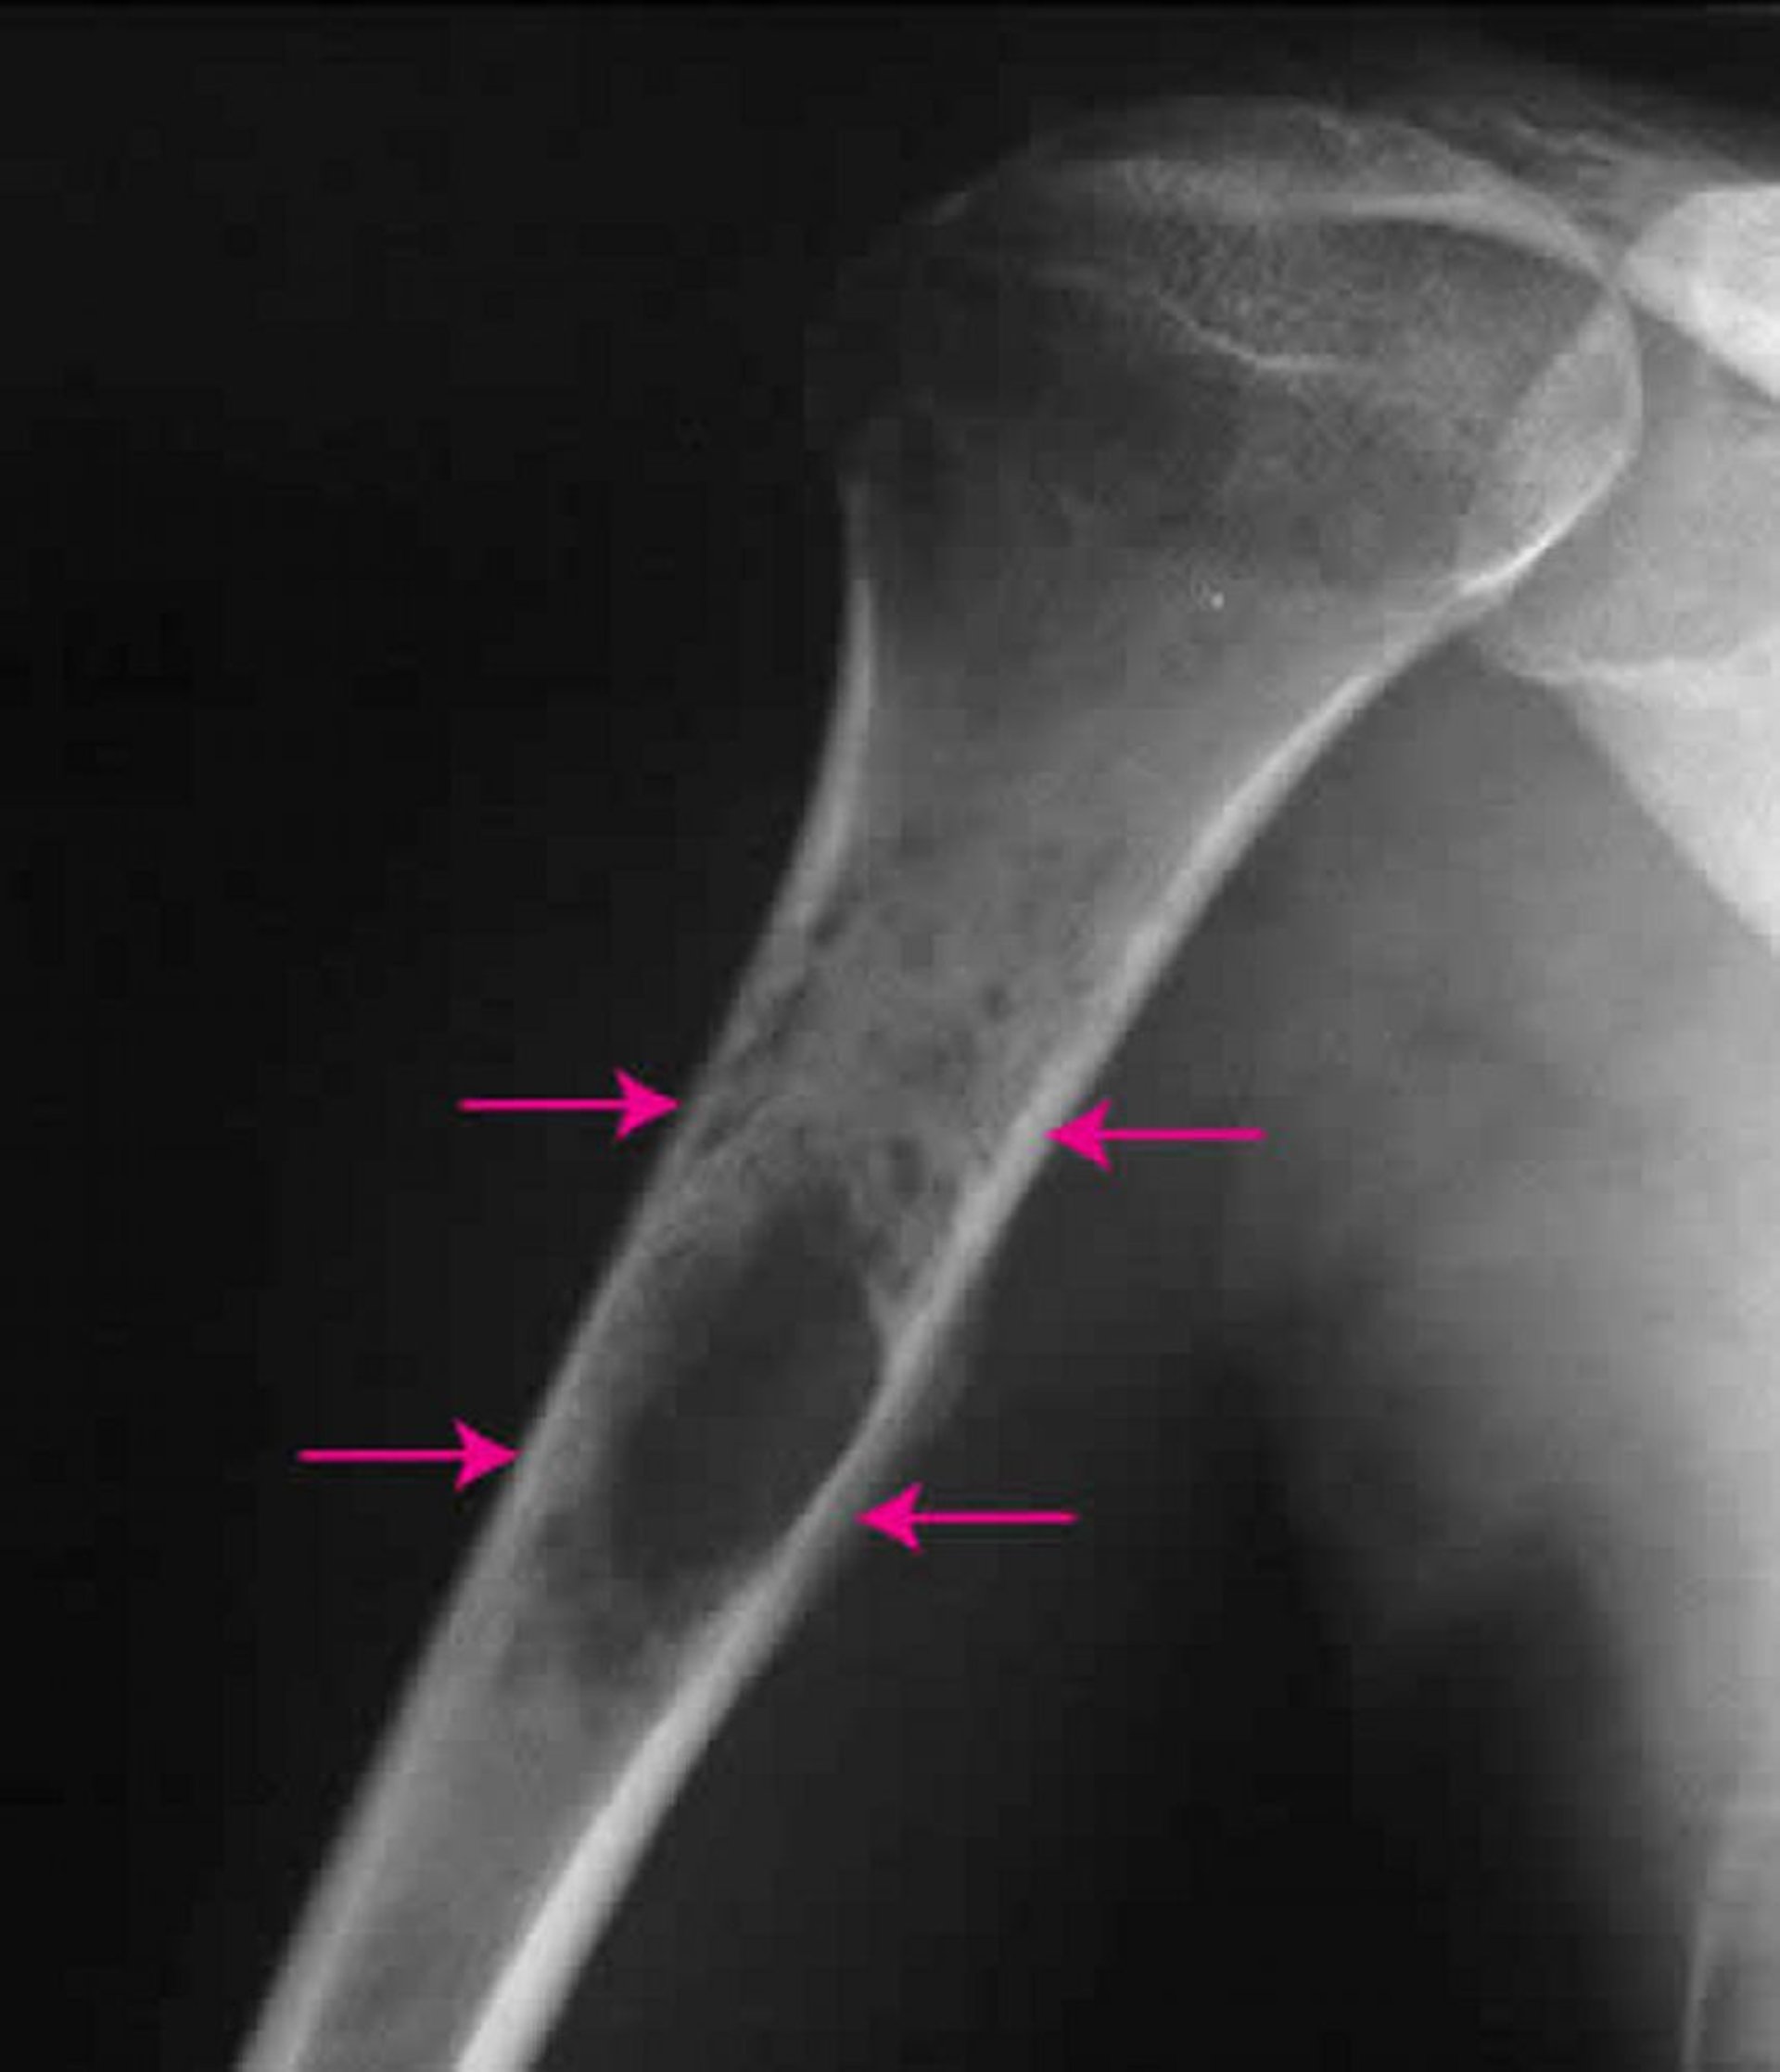

Sarcoma de Ewing ósseo

Esta radiografia do ombro mostra um sarcoma de Ewing (setas) dentro do osso do braço.

Imagem por cortesia do Dr. Michael J. Joyce e do Dr. Hakan Ilaslan.